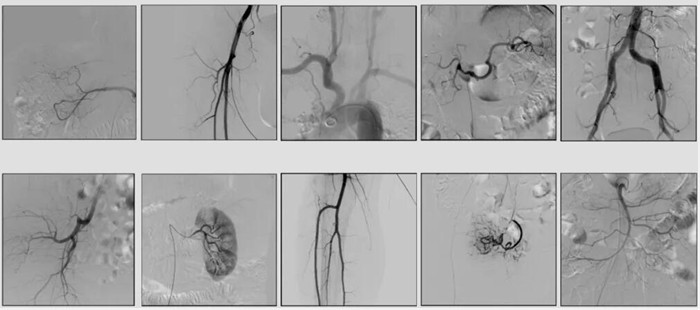

2)中C,學(xué)名外周介入C形臂(Peripheral Interventional C-Arm)。與小C相比,中C不僅大幅提高了X射線系統(tǒng)功率,更重要的是增加了減影等血管機(jī)相關(guān)功能,基本可以完成80%的介入手術(shù)需求,主要應(yīng)用在周圍血管科、消化內(nèi)科、婦科、整形科等領(lǐng)域。

中C在周圍血管領(lǐng)域有重要價值